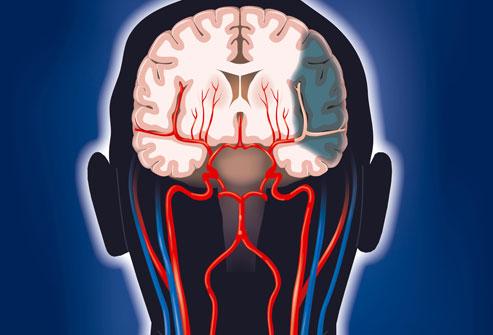

腦梗是一種常見的腦血管疾病,具有高發(fā)病率、高致殘率和高死亡率的特點(diǎn),腦梗是指局部腦組織因血液循環(huán)障礙,導(dǎo)致缺血、缺氧而發(fā)生的軟化壞死,本文將詳細(xì)介紹腦梗的各個(gè)方面,幫助讀者更好地認(rèn)識(shí)這一疾病。

腦梗,即腦梗死,是一種由于腦部血液供應(yīng)障礙導(dǎo)致的局部腦組織缺血、缺氧,進(jìn)而引起腦組織軟化及壞死,腦??煞譃槟X血栓形成、腦栓塞和腔隙性梗死等多種類型。